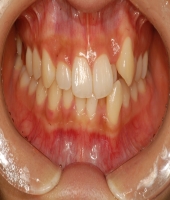

| ● 진료과목 : [심미보철] 돌출치아의 치료

| ● 내용 : 사고로 인한 돌출치아의 치료 |